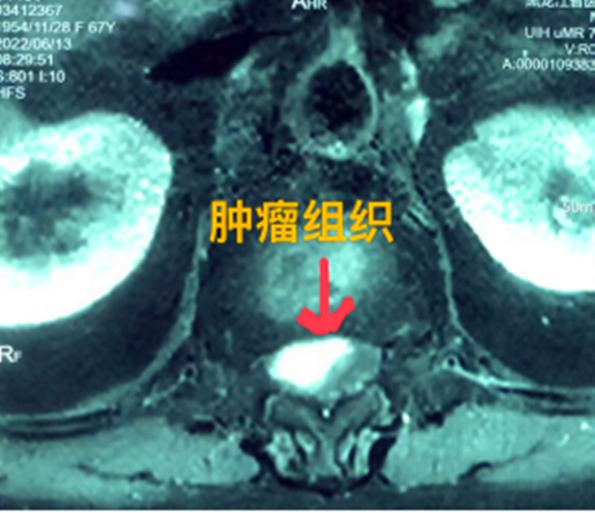

據(jù)省醫(yī)院神經(jīng)外一科陶宇醫(yī)生介紹,家住外地的張大娘最近總感覺雙下肢疼痛、無力,且排尿困難及便秘,伴有行走困難。時(shí)間長(zhǎng)了,張大娘病情逐漸加重,劇烈的疼痛甚至讓她無法完整入睡。在當(dāng)?shù)蒯t(yī)院,張大娘按腰椎肩盤突出接受治療,但未見好轉(zhuǎn),隨后進(jìn)行的胸椎MRI(核磁共振)檢查,結(jié)果不禁讓張大娘和家屬瞠目結(jié)舌,原來張大娘患的竟然是少見的脊髓腫瘤。

張大娘住進(jìn)了黑龍江省醫(yī)院神經(jīng)外一科,該科孫國(guó)章主任醫(yī)師熱情地接待了張大娘,并邀請(qǐng)骨外一科專家共同為她進(jìn)行了聯(lián)合會(huì)診。發(fā)現(xiàn)張大娘病情十分復(fù)雜棘手,脊髓腫瘤體積較大,充滿髓腔且神經(jīng)已經(jīng)完全受壓,需要手術(shù)來完整切除。同時(shí)還發(fā)現(xiàn)張大娘的胸腰部曾受過兩次外傷,伴有多處骨折,這對(duì)接下來的手術(shù)操作帶來一定影響。